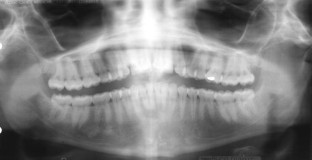

Fig. 3